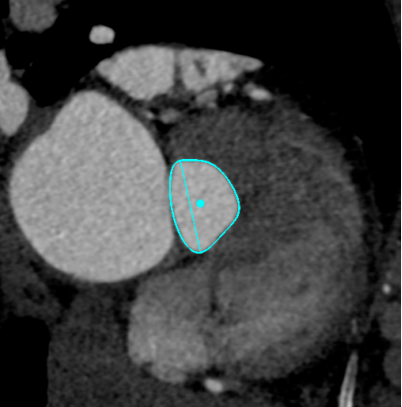

30%收缩期

Annulus

长径: 24.8 mm

周长: 68.6 mm

面积: 352.3 mm²

LVOT

长径: 24.3 mm

周长: 66.3 mm

面积: 321.7 mm²

SOV

27.3 x 25.8 x 25.9 mm

STJ

长径: 27.6 mm

周长: 84.4 mm

面积: 566.2 mm²

高度: 13.8mm

升主动脉

长短径:39.7x37.6mm

(距瓣环40mm)

RCA

下缘高度 10.2mm

上缘高度 11.9mm

瓣叶长度 12.7mm

LCA

下缘高度 7.1mm

瓣叶长度 11.8mm

● 冠脉开口高度低,结合窦部高度和宽度、STJ大小、瓣叶长度等,冠脉闭塞风险高,根据预扩张结果决定是否行冠脉保护。